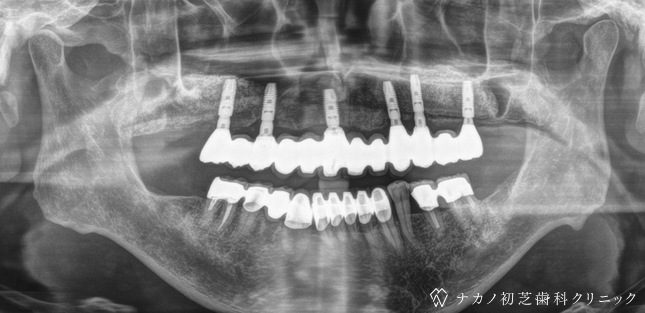

インプラント・13本 (60代女性)

BEFORE

AFTER

年齢 60代女性

治療内容 インプラント治療13本(骨造成の併用)

インプラント治療とは、歯を抜いた所にチタン製の人工歯根を埋入し、その上に歯を入れる方法です。骨を増やすことで、より審美的に治療が出来ました。費用 1本 400,000円(税込 440,000円)

リスク・副作用

腫れ・疼痛・違和感を感じるなどの症状を生じることがあります。